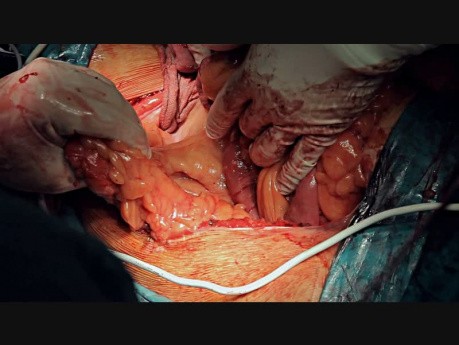

Ostre rozdęcie okrężnicy nakładające się na rzekomobłoniaste...

Ze względu na niekontrolowany i masywny krwotok pacjent przeszedł kolektomię. Widoczny fragment usuniętego jelita grubego.